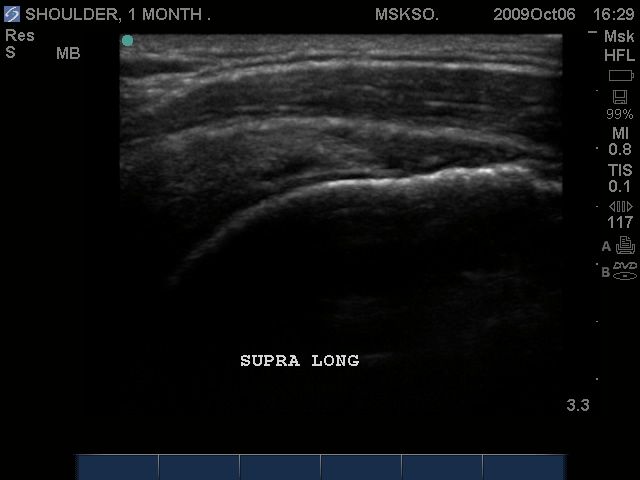

Long axis Supraspinatus tendon over lateral Greater Tuberosity. (lateral greater tuberosity is flat relative to the anterior) Tendon retraction is seen over cartilage interface sign of the humeral head.